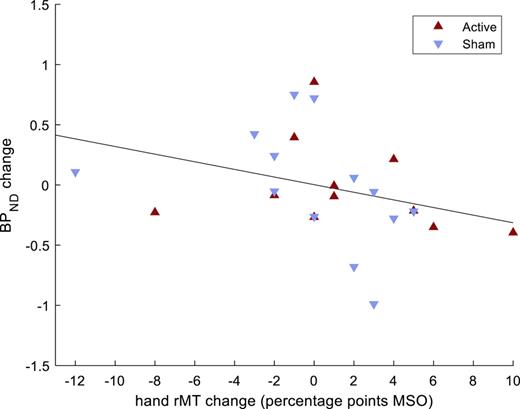

The results from the pre-post change analyses are shown in Table 4. Changes in M1 sphere BPND, between pre- and post-assessments, were inversely correlated to pre-post changes in hand rMT (Fig. 2). This result remained significant after adjusting for multiple comparisons. The correlation between changes in BPND and hand rMT did not differ between those receiving active or sham treatment (z = 0.38, p = 0.7). No correlations were detected between pre-post change in M1 sphere BPND and pre-post changes in SICI, LICI, or ICF.

Correlation between pre- and post-assessment changes in non-displaceable binding potentials (BPND) in hand motor cortex and pre-post changes in hand resting motor threshold (rMT), in patients with a major depressive episode. N = 24 (4 patients lacked post-assessments). MSO, maximum stimulator output.

Correlation between pre- and post-assessment changes in non-displaceable binding potentials (BPND) in hand motor cortex and pre-post changes in hand resting motor threshold (rMT), in patients with a major depressive episode. N = 24 (4 patients lacked post-assessments). MSO, maximum stimulator output.